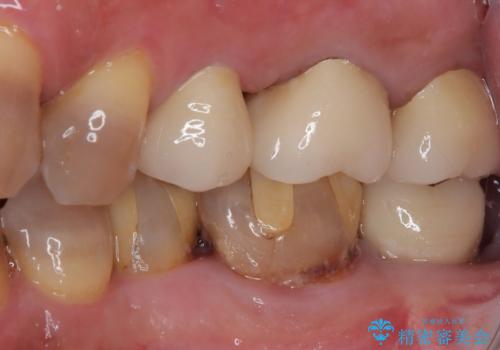

- 詰め物が欠けてしまい、虫歯かもしれないから診てほしいとのことで来院された患者様です。

精査の結果、詰め物の下に虫歯が大きく広がっているのがわかりました。

虫歯の範囲が大きく、部分的な詰め物では対応が難しいため、オールセラミッククラウンにて補綴することとしました。

また虫歯除去の際に、万一根管と交通してしまっても根管に感染を起こさないために、ラバーダム防湿をして虫歯除去しました。